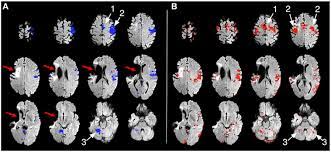

Next, carmichael and segura plan to investigate whether brain tissue can be regenerated in mice long after the stroke injury. This phenomenon, known as neuroplasticity, is considered to be one of the most important developments in modern science for our understanding of the brain. Research shows that the brain possesses an extraordinary ability to heal itself after stroke. This ability, known as neuroplasticity, is why many stroke survivors go on to make astonishing recoveries. In humans, it's two months. One day after head injury (left), bright dye along the edge of the brain suggests damage to the meninges, or the brain's protective lining. A patient should start rehabilitation as early as possible after a stroke. He is still improving 37 years after the stroke.

The amount of recovery depends on many factors, including the part of the brain that is damaged, the size of the damaged area, and how well the brain's neuroplasticity processes work. And while much is known about. After 35 days (right), the dye no longer appears, indicating the meninges may have healed. It requires your help to activate it. No two strokes are alsike and recovery depends on how the brain itself can recover.